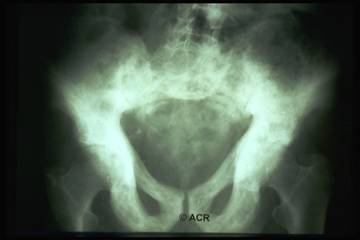

Reperti radiografici

Lisi ossea: riflette l'aumentata attività osteoclastica;

Sclerosi: riflette l'aumentata attività osteoblastica;

Aumento volumetrico dell'osso;

Lesioni litiche a "fiamma": riscontrabili a carico delle ossa lunghe;

Utile anche la scintigrafia ossea: può aiutare nel determinare l'estensione del coinvolgimento osseo, tuttavia non dovrebbe essere usata per porre diagnosi.